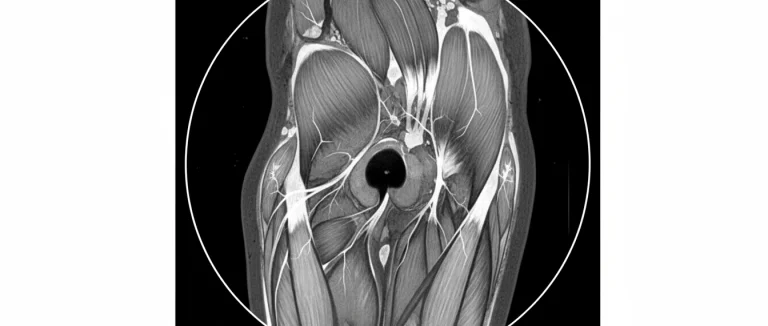

- МРТ (магнитно-резонансная томография) – золотой стандарт для определения объёма разрыва и наличия сопутствующих повреждений.

В Лив Хоспитал применяется современное оборудование, включая 3‑Тесла МРТ‑сканер, который обеспечивает детализированное изображение мягких тканей. Это позволяет точно определить, является ли травма лишь растяжением или полным разрывом, а также выявить наличие кровоизлияний или гематом.